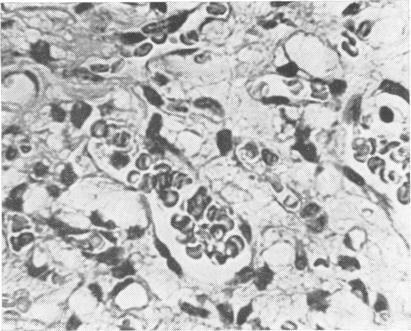

A retrospective study has been carried out on 67 patients harbouring 78 posterior fossa haemangioblastomata. The site, macroscopic nature, and histological features are described, and correlations sought with the degree of erythrocytosis in the peripheral blood. The problems of aetiology are discussed and a single hypothesis advanced.